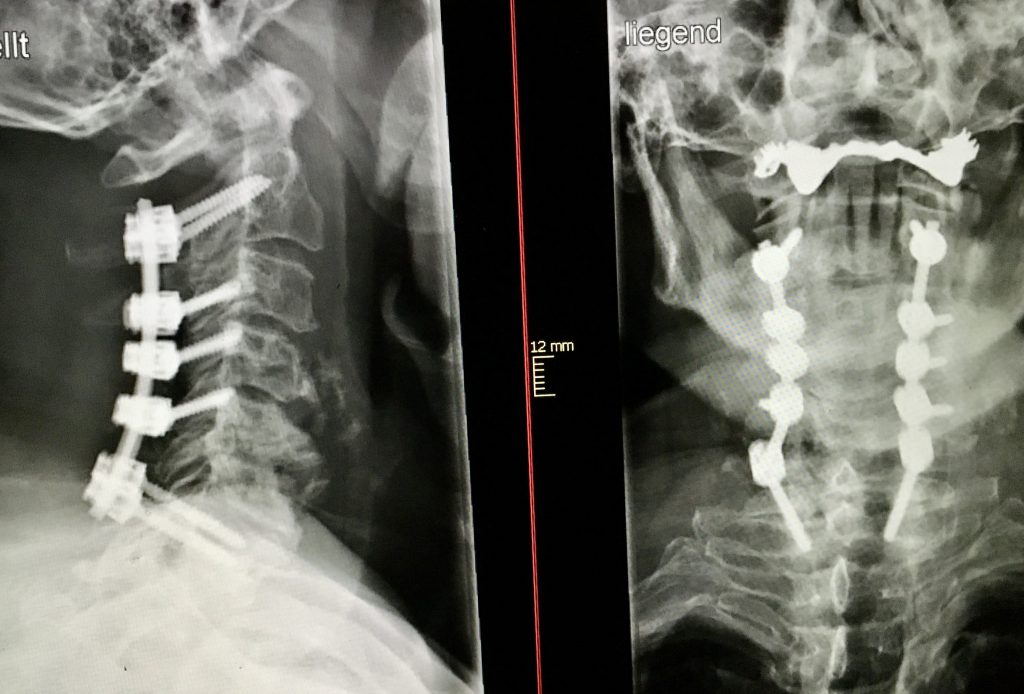

La artrodesis cervical posterior se realiza a través de una incisión media en la cara posterior del cuello; se implantan tornillos en las vértebras, los cuales se unen por unas barras. Para conseguir una liberación de la médula espinal se resecan los arcos vertebrales a nivel de la zonas comprimidas.

Puede realizarse por vía anterior o posterior, y en casos severos pueden combinarse las dos vías. La artrodesis cervical anterior es la más habitual y se realiza con una incisión en el flanco lateral anterior del cuello, y desde la misma se retiran los discos deteriorados y se descomprime la médula.